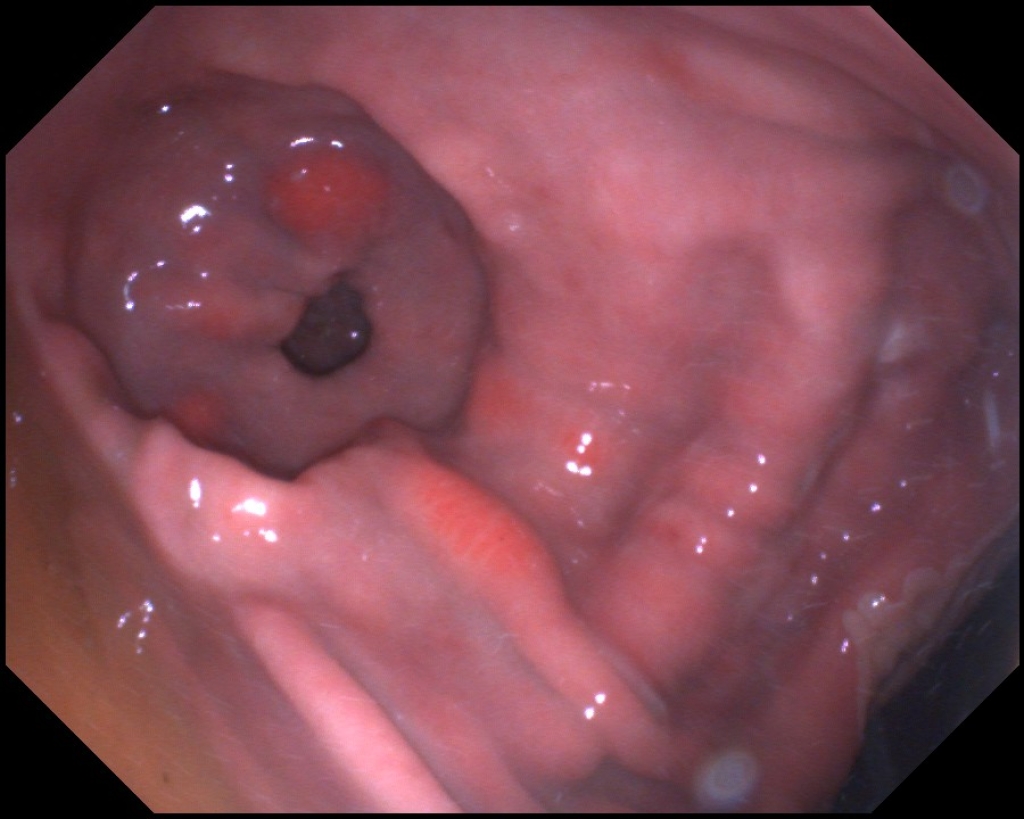

Maagulcera in het onderste gedeelte van de maag zien we wat minder vaak en zijn moeilijker om te behandelen. Ondanks wetenschappelijk onderzoek weten we  eigenlijk nog niet goed waarom  deze maagzweren ontstaan. Bij mensen komen vergelijkbare maagzweren voor, deze zijn veelal het gevolg van medicijn gebruik of een bacteriële infectie van de maagwand. Bij paarden is wel uit onderzoek gebleken dat bacteriën geen grote rol spelen in het ontstaan. Ook hebben veel paarden met dit type maagzweren geen medicijnen gebruikt die dit kunnen veroorzaken. Wat de achterliggende oorzaak is voor het ontstaan van deze zweren is dus nog niet goed bekend. Overigens is bij 30% van de maagzweren bij mensen de oorzaak ook niet bekend. Dit maakt dat deze maagzweren vaak lastiger te behandelen zijn en een langdurige behandeling vergen.

Links: Diepe maagzweren in het onderste gedeelte van de maag

Rechts: Maagzweren onderin de maag rondom de uitgang naar de dunne darm

Diepe maagzweren in het onderste gedeelte van de maag

Maagzweren onderin de maag rondom de uitgang naar de dunne darm